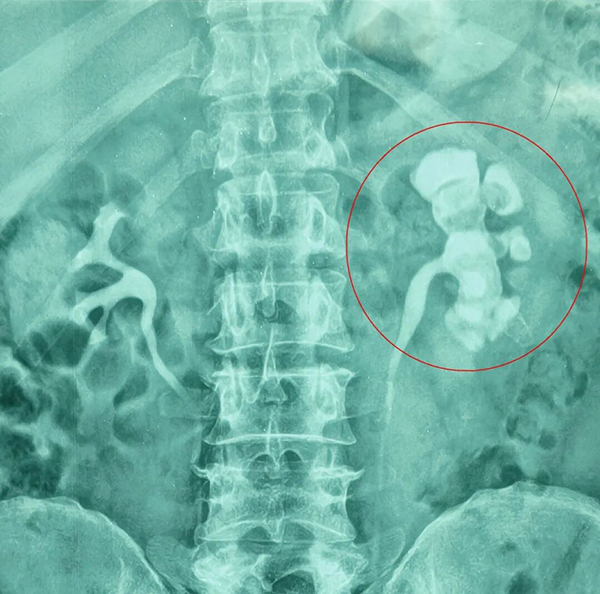

入院检查显示,其左肾多发结石,且位置分散,较大者约0.8×0.5厘米。贵阳市卫健局2019贵阳市优秀医师、贵阳结石病医院泌尿外科王华勋主任带领团队,经过详细评估,为任先生制定了“经皮肾镜碎石取石术”手术方案。

手术中,王华勋主任利用国际领先的铥激光碎石系统,把任先生的多发性结石逐一高效粉末化,同时结合智能负压清石系统,实现“边碎边吸,即时清空”,在精准清除结石的同时,最大程度保护了肾脏功能。